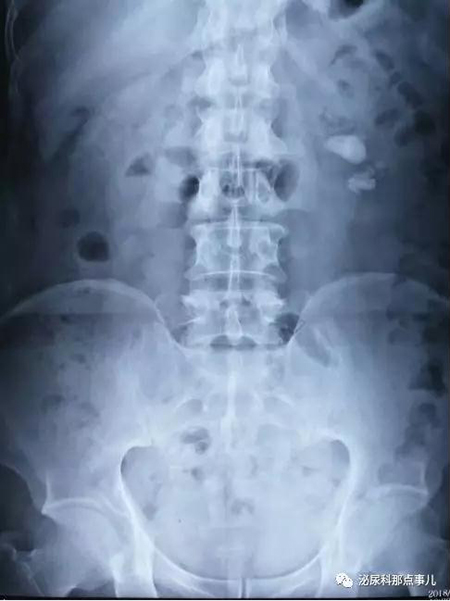

术前KUB